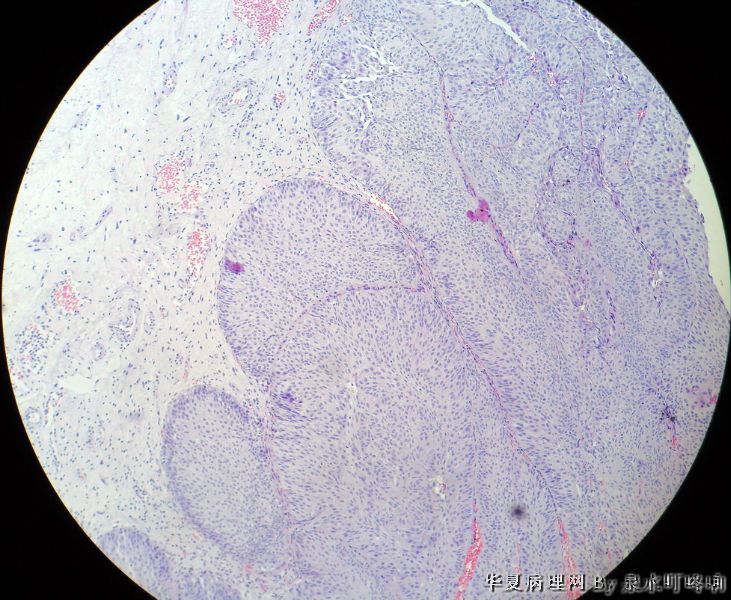

膀胱肿物

男,76岁,血尿一个月,发现膀胱肿物,行切除术,肿物位于右侧膀胱后外侧壁,约1.5×1.5×1.5厘米。

大体:灰白肿物一个,大小约2×1.1×0.9厘米,切面灰白,质中。

尿路上皮癌,低级别。

低级别非浸润性乳头状尿路上皮癌

(膀胱)非浸润性乳头状尿路上皮癌,低级别

低级别尿路上皮癌。至于浸润的问题还请楼主仔细观察切片,总感觉那种推进式的生长模式有浸润的嫌疑,临床上浸润与否治疗方式是不一样的。

Dx: High grade papillary urothelial carcinoma because: 1. nuclear chromasia (fig 13) and coarse chromatin. 2, almost all nuclei have prominent  nucleoli. 3, Nuclear pleomorphism (some nuclei are three times larger than smaller ones). 4. Nuclear membrane irregularity. 5. mitosis can be seen far away from the basement membrane. 6. a good portion of the neoplastic cells loss orientation that should be perpendicular to the basement membrane. 7. Low power view shows papillary branching and fusion. 8. patient's age

However, this should be the low end of the spectrum of high grade urothelial carcinoma. Careful search might reveal some focal microinvasion.or urothelial carcinoma in situ.